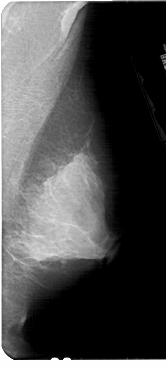

A_1927_1.RIGHT_MLO

LEFT_MLO LINES 5326 PIXELS_PER_LINE 2386 BITS_PER_PIXEL 12 RESOLUTION 43.5 OVERLAY